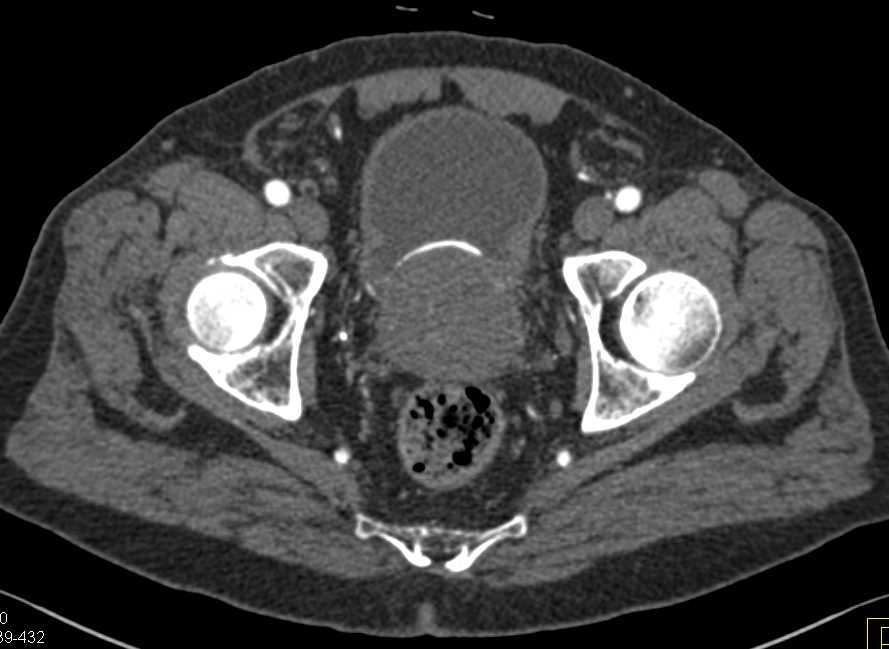

Testicular Trauma